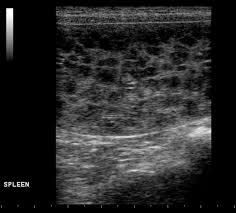

What Causes Spleen Cancer In Dogs - Spleen Cancer In Dogs Cats Long Beach Animal Hospital - Like many forms of cancer in dogs, we are unsure of the underlying cause of mast cell tumors, but certain breeds seem to be more at risk for developing them.;. Many other types of tumors, both benign and malignant, can occur in the spleen. The spleen is an organ that will store blood and will also supply blood to other organs, while cleaning blood cells as well. Often, owners do not realize their dog is affected until the sudden hemorrhage or collapse. This cancer is typically diagnosed via fine needle aspiration. If the above describes your dog's situation, then the immediate option is surgery.

Malignant lymphoma is one of the most common types of cancer that affects dogs. While the specific cause (s) for spleen cancer in dogs is unknown, we know that there must be some genetic factors, as certain breeds seem to be affected more than others. Hemangiosarcomas are fed by the blood vessels and fill with blood. Any large breed dog appears to be at an increased risk especially german shepherds, golden retrievers, labradors, and poodles. This cancer metastasizes at a rapid rate and affected dogs have limited survival time.

This cancer metastasizes at a rapid rate and affected dogs have limited survival time. Many other types of tumors, both benign and malignant, can occur in the spleen. Because of this, the tumor can rupture, leading to sudden and severe hemorrhage, collapse, and rapid death. It is the tumor of cells that line blood vessels, but most commonly affects heart, spleen, liver or skin. The spleen is an organ that will store blood and will also supply blood to other organs, while cleaning blood cells as well. Spleen and liver hemangiosarcoma in dogs. In some cases, one cause for the enlargement and inflammation of the spleen is a condition known as eosinophilic gastroenteritis. Hemangiosarcomas are fed by the blood vessels and fill with blood. Dogs with hemangiosarcoma in the spleen may not show any symptoms at the early stage. These causes include splenic torsion due to torsion causing the blood flow to be cut off, acute canine infectious hepatitis, salmonellosis and some types of spleen cancer (splenic lymphoma, splenic hemangiosarcoma). In this condition, cells and other substances from other parts of the body start to infiltrate into the spleen and cause an enlargement. This cancer is typically diagnosed via fine needle aspiration. If you notice your dog shedding pounds, either rapidly or slowly, make an appointment with your vet.

Hemangiosarcoma of the spleen is the most common cancer of the spleen in dogs. There are only limited treatment options. If you notice your dog shedding pounds, either rapidly or slowly, make an appointment with your vet. Lymphoma may also cause changes to the eyes and internal organs. It's rare for a dog owner to even know the tumor is there until it ruptures.

Spleen and liver hemangiosarcoma in dogs. The cellular lining of the blood vessels play an important role in the development of splenic masses. Lymphoma can affect any breed of dog, but. Symptoms of spleen and liver hemangiosarcoma in dogs This cancer metastasizes at a rapid rate and affected dogs have limited survival time.